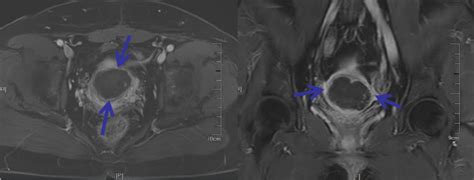

由于切口愈合不良,产褥期可出现反复阴道流血。如慢性失血可致贫血,如为短期内大量出血,可造成休克或产妇死亡。孕妇剖宫产术后体温升高,持续血性恶露,妇科检查可见子宫大而软,宫颈口松,子宫内口可触及裂口的薄弱处或肠线,下腹部有固定压痛。诊断时不宜行官腔探查及诊断性刮宫,B超检查可见到与子宫不可分开的异常回声区。